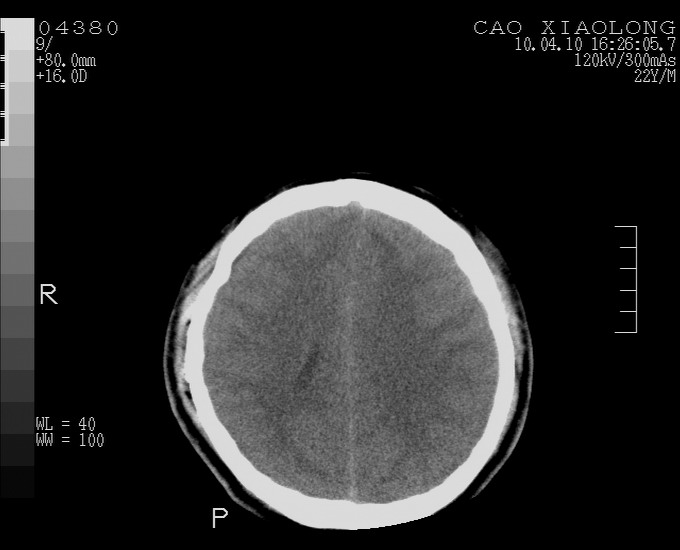

以下是引用随光逐影在2010-4-11 11:00:00的发言:[br]1)左侧额颞顶部硬膜下血肿。2)蛛网膜下腔出血。3)右侧颞顶部颅骨线形骨折。[br][br]20小时后复查:左侧额颞叶脑挫裂伤;左侧额颞顶部硬膜下血肿及蛛网膜下腔出血有吸收表现;右侧颞顶部颅骨线形骨折。[br]